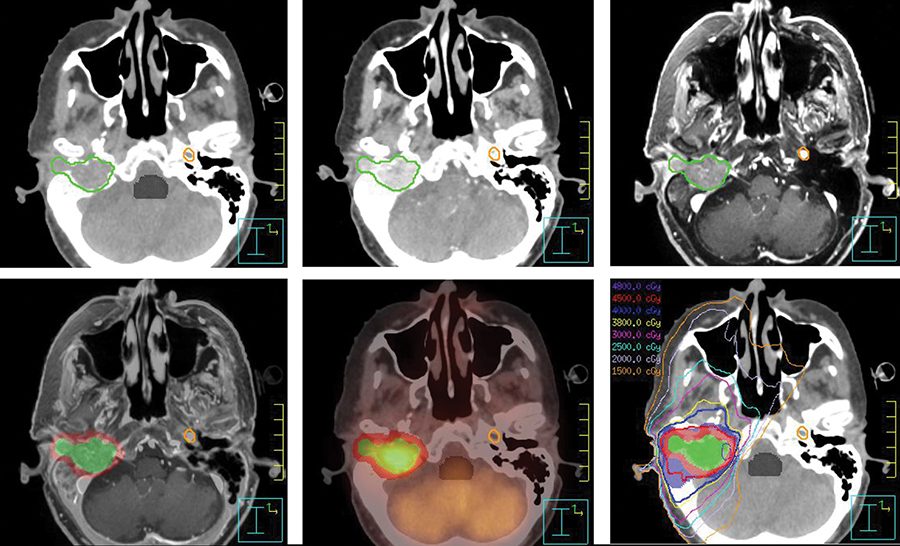

Our radiation oncologists are experts in the treatment of skull base tumors. They have pioneered the use of modern high-precision radiation therapy techniques that target radiation doses precisely to the shape of tumors. These treatments minimize side effects, damage to healthy tissue and long-term toxicity.

Radiation treatment for skull base tumors at MD Anderson can include specialized techniques. Among these are stereotactic radiosurgery, which delivers a powerful dose of treatment radiation in a single session; and proton therapy, a state-of-the-art treatment that is not widely available. There’s even a radiation clinic for patients with recurrent skull base tumors. These patients can benefit from our multidisciplinary team approach to managing complex cases.

Treatment for tumors of the skull base may involve surgery, radiation therapy, chemotherapy or a combination of therapies. Surgeons in the Skull Base Tumor Program use both open and minimally invasive diagnostic and surgical approaches, depending on each patient's unique characteristics. For patients with tumors that are responsive to irradiation, radiation oncologists plan three-dimensional treatment algorithms for the precise delivery of radiation therapy.